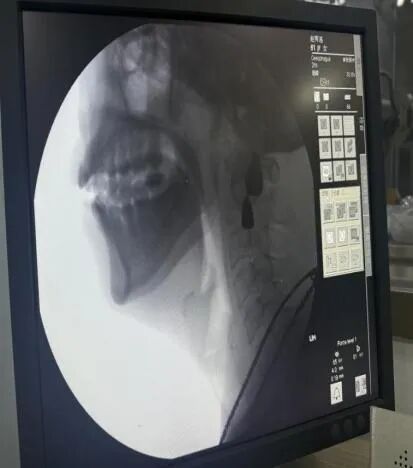

我院五疗康复科成功开展吞咽造影检查新技术:吞咽障碍诊断的“金标准”——吞咽造影检查(VFSS)

近日,我院五疗康复科联合医学影像科开展了院内首例吞咽障碍诊断的“金标准”吞咽造影检查(VFSS),并为多名脑血管病合并吞咽障碍患者完成吞咽造影检查,此项技术的开展标志着我院在吞咽障碍评估手段日趋完善,康复诊断更加精准,康复评定工作更上一层楼,为治疗吞咽障碍患者带来了福音和希望。

吞咽造影检查(VFSS)是在X线透视下,针对口、咽、喉、食管的吞咽运动所进行的吞咽检查,是目前公认最全面、可靠、有价值的吞咽功能检查法,是诊断吞咽障碍首选和理想的方法,是客观评价吞咽障碍的“金标准”,对指导临床吞咽障碍治疗具有重要意义。